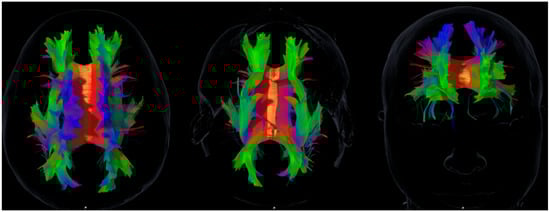

Diffusion Basis Restricted Fraction as a Putative Magnetic Resonance Imaging Marker of Neuroinflammation: Histological Evidence, Diagnostic Accuracy, and Translational Potential -